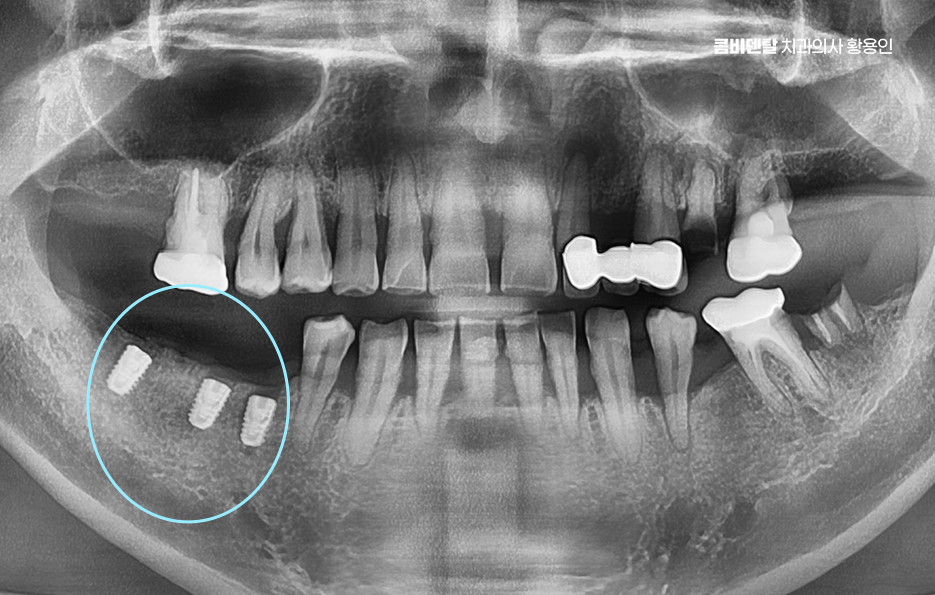

일반적으로 발치 후 뼈 상태가 양호하다면, 약 2~3 개월 정도의 치유 기간을 거친 다음 임플란트를 심게 되는데 요즘은 상황에 따라 바로 임플란트를 식립하는 ‘즉시 식립’ 방식도 많이 사용되고 있으며 단, 이러한 치료 방식은 뼈의 상태가 충분히 튼튼하고 염증이 없는 경우에 가능하며 경험 많은 치과의사와 함께하는 것도 중요할 수 있었어요

치아 발치 후 임플란트 치료 과정은 처음에 CT나 파노라마 엑스레이를 통해 뼈의 양과 밀도, 신경 위치를 정확히 확인하는 것부터 시작되며 치아가 빠진 자리에 뼈가 많이 흡수되어 있다면, 임플란트를 심기 전에 뼈이식을 먼저 해야 할 수 있지만 반대로 뼈 상태가 좋다면 임플란트를 심고, 보통 3개월 동안 뼈와 잘 붙을 때까지 골융합 과정을 기다리게 되며 골융합이 잘 이루어진 뒤에는 그 위에 지대주라는 연결 부품을 끼우고, 그 위에 최종 보철물을 씌우면서 치료가 마무리되고 있어요